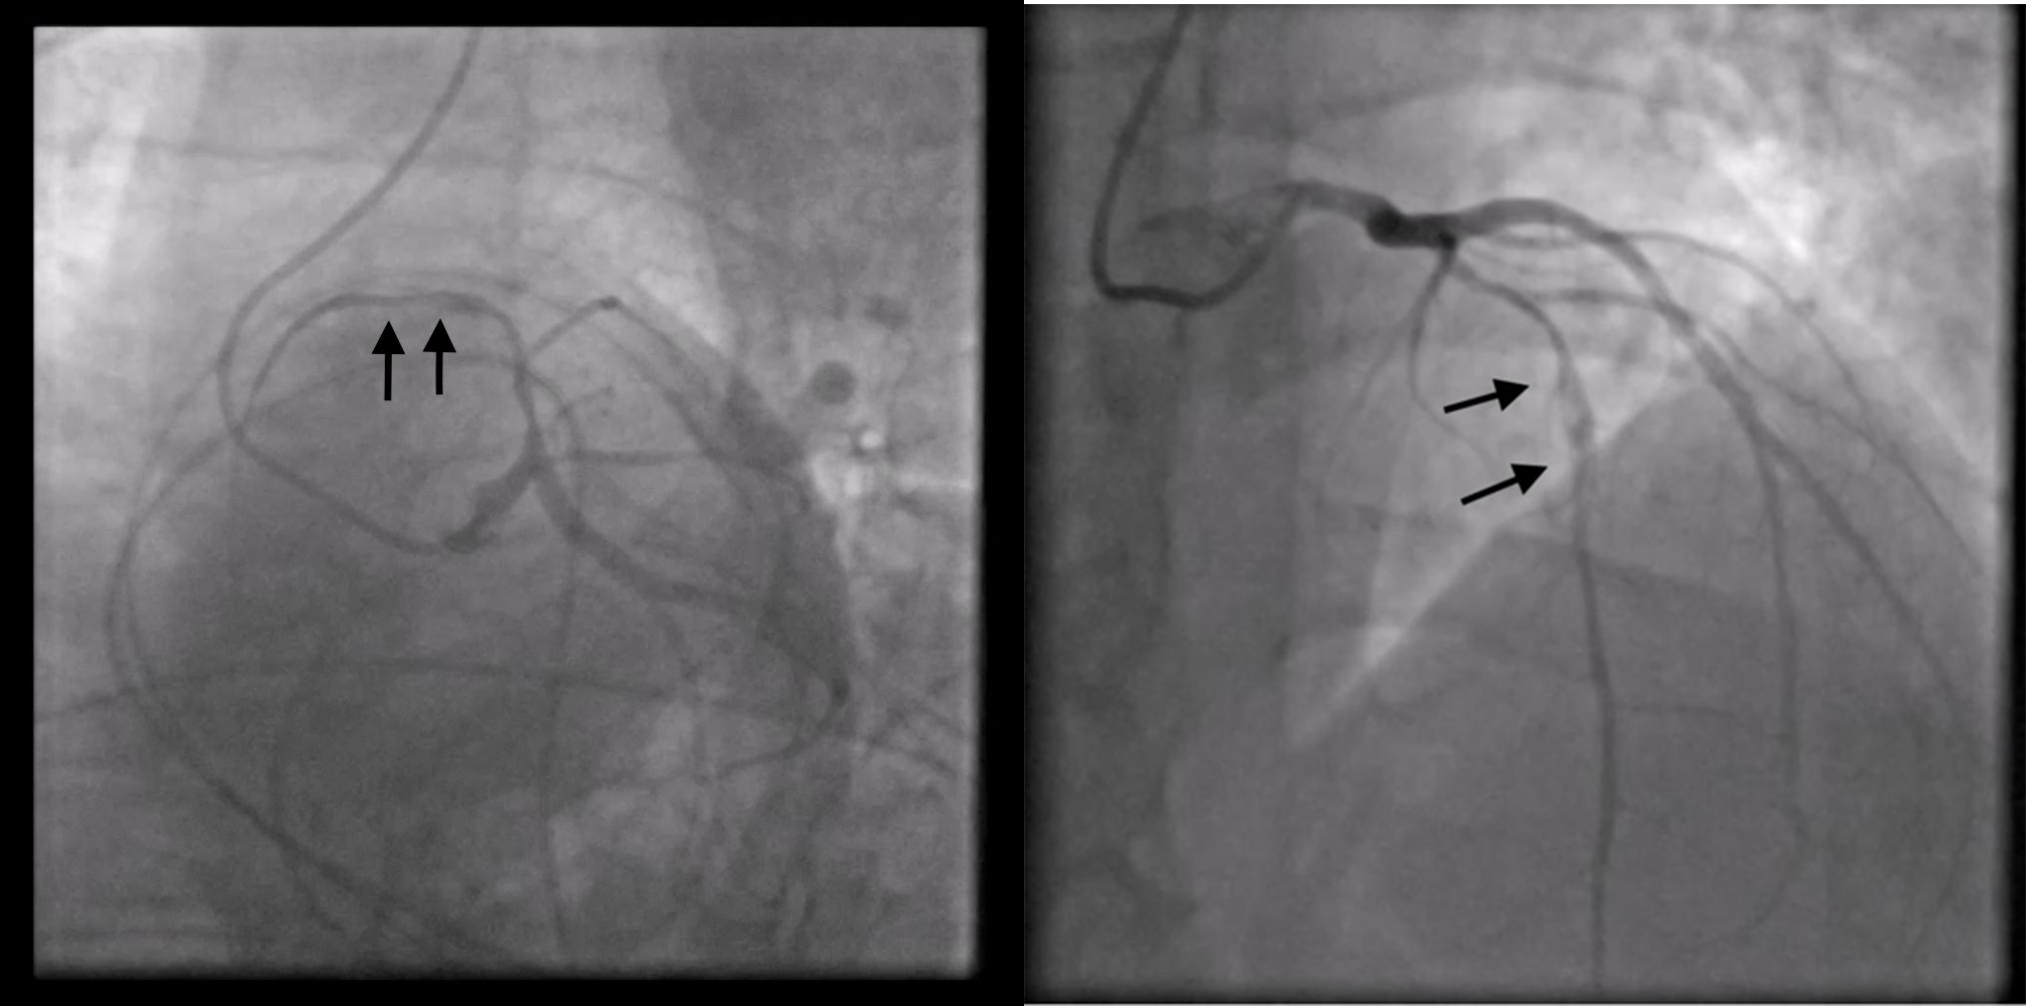

The new hs-troponin test results, showing a new peak of myocardionecrosis markers of 289 ng/L, came when the patient had already been transferred to the CICU, where, finally, an emergency coronary angiography (CAG) was performed. Surprisingly enough, the CAG showed no stenosis; instead, it revealed a spontaneous dissection evident in the middle tract of the LAD coronary artery; this was classified as a type 2 dissection of the LAD coronary artery according to the European Society of Cardiology (ESC) classification (Fig. 6). The angiographic images show a plausible proximal extension of the dissection, where the vessel appears diffusely reduced in caliber; however, the same findings could also be indicative of diffuse atherosclerotic disease in the proximal LAD artery. In the acute setting, given the high suspicion of proximal extension, it was not deemed appropriate to use intracoronary imaging techniques such as intravascular ultrasound (IVUS) or optical coherence tomography (OCT) because of the associated risks of catheter-induced dissection propagation, potentially aggravating the patient’s condition and endangering her life.

Fig. 6.

Fig. 6.Coronary angiography shows no stenosis; instead, it reveals a spontaneous type 2 dissection of left anterior descending (LAD) coronary artery.